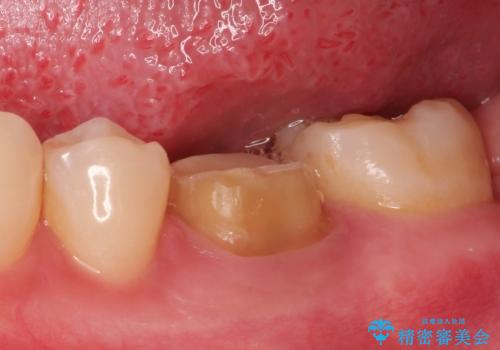

- 下の奥歯の銀歯を白くしたいとのことで来院されました。

痛みなどの症状はなく、前に根管治療を行っている歯になります。

古い銀歯を除去し、審美性の良いセラミッククラウンでの治療を行うこととしました。